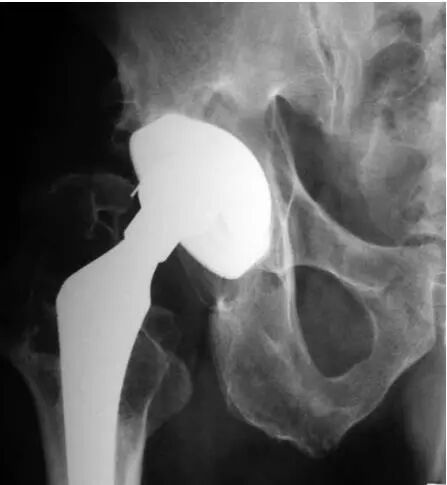

图5:A和B,一名57岁女性的左髋部X光片。A:无骨水泥全髋关节置换术后7年的正位X线片显示,由于聚乙烯磨损,股骨头关节偏心,大转子移位骨折并伴有溶骨性病变(箭头)。B:X线片,髋臼假体翻修8年后,用双张力带钢丝固定大粗隆并植入同种异体骨,显示大粗隆良好愈合和同种异体骨融合。

图6:A和B,一位69岁男性假体周围骨盆骨溶解,无骨水泥全髋关节置换术后12年的大转子和小粗隆的右髋位X线片。A:翻修手术前的x光片。B组:髋臼假体翻修一年后行大转子切开复位内固定,2根张力带钢丝和1根斜环扎钢丝,辅以异体骨移植,显示大转子骨折愈合。